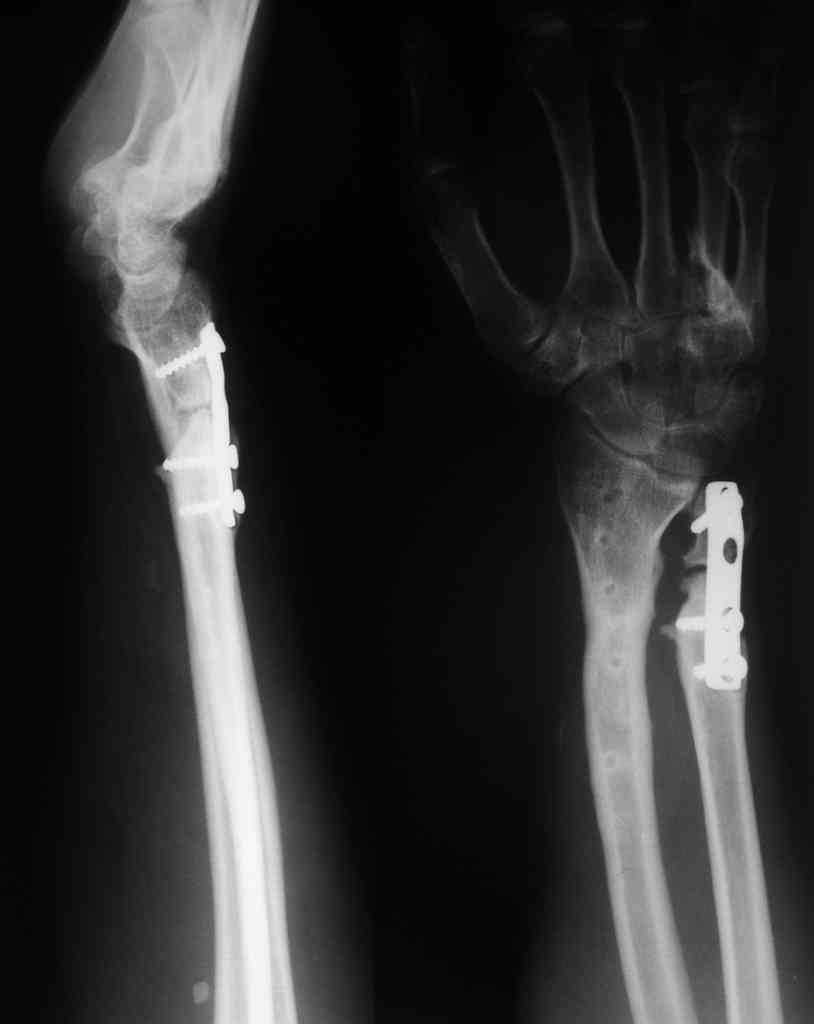

У больного/ой кроме перелома лучевой кости и шиловидного отростка локтевой, разрыв дистального радиоульнарного сочленения, перелом ладьевидной кости и ладьевидно-полулунная диссоциация.

Если позволите свое мнение, не стал бы лечить аппаратом эту травму, перелом луча не консолидировался: открытая репозиция+ костная пластика+ пластина, синтез ладьевидной кости, по возможности шов ладьевидно полулунной связки,

если восстановить связку не представляется возможным, фиксация 2 спицами.

Судя по показанным Рг граммам, очевиден посттравм. артроз лучезапястного сустава, проблема дистального радиоульнарного сочленения(TFCC).

Угол наклона лучевой фасетки в норме в пределах 10-15 градусов, на представленном боковом снимке -может быть чуть больше 15градусов. Выполнив

разгибательную остеотомию луча, ты поставишь фасетку в нейтральное положение и таким образом увеличится угол разгибания , но уменьшится сгибание. По сути, амплитуда движений останется такой же.

Первым этапом я бы убрал пластину с последующей ограниченной резекцией головки локтевой кости(hemiresection and interposition arthroplasty Bowers technique). провести курс реабилитации. если уровень мобильности сустава не

будет устраивать больного, можно рассмотреть проксимальную карпальную резекцию в качестве последующего этапа.